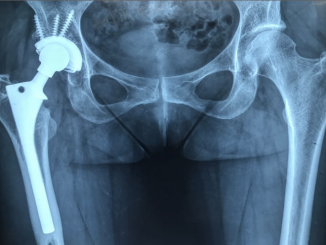

Prótese de quadril: um aliado que devolve qualidade de vida para pacientes

A prótese de quadril é recomendada como tratamento para quem tem artrose no quadril, uma doença que tem como característica o desgaste da cartilagem, atingindo a mobilidade além de trazer dor e desconforto. Se não